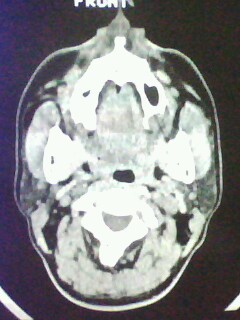

以下是引用随光逐影在2009-5-20 19:22:00的发言:[br]1)考虑左上颌骨近中线区含牙囊肿。2)鼻中隔右突偏曲。3)双侧下鼻甲肥大。